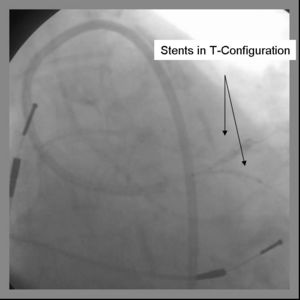

5) The 2nd stent is advanced into the parent vessel and placed across the side branch.

6) The side branch stent is deployed. (Another option is to place a balloon in the parent branch and inflating to low atm while pulling the side branch back. This may help ensure adequate coverage of the ostium.

8) The parent stent is deployed across the side branch.

9) Angiography should now be performed to ensure adequate side branch coverage and stent deployment. The parent stent is deployed.